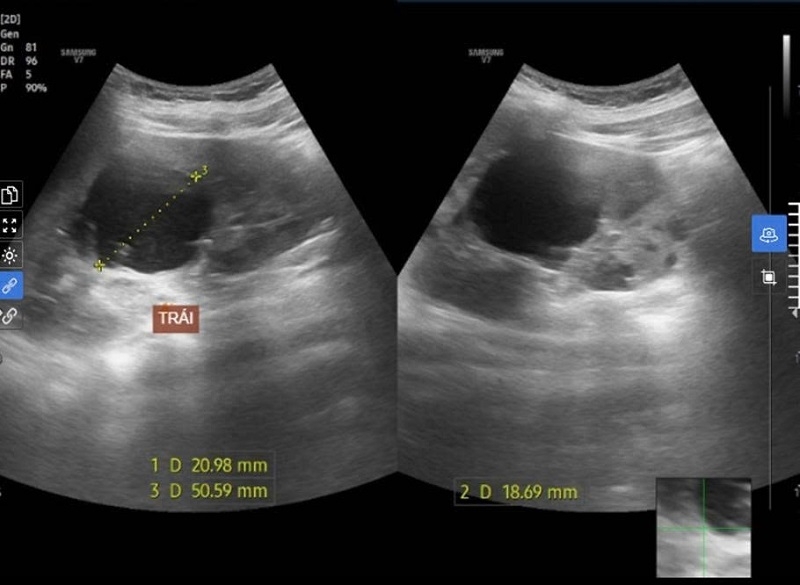

Hình ảnh nang thận trái của nam bệnh nhân ghi nhận trên siêu âm.

Kết quả cho thấy thận hai bên xuất hiện nhiều nang (thận trái >7 nang, thận phải >10 nang), kích thước thận to hơn bình thường. Dù chưa có biểu hiện suy thận (Creatinin: 53.16, eGFR: 195 ml/ph/1.73 m²), song em được chẩn đoán mắc bệnh thận mạn giai đoạn 1 – giai đoạn sớm nhất, chưa gây tổn thương chức năng thận.